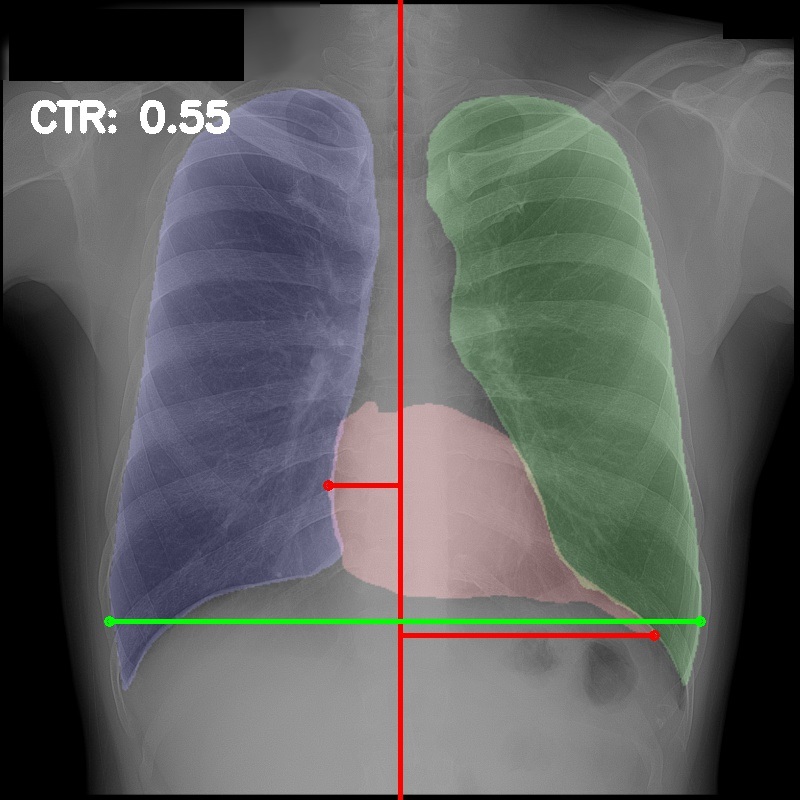

3.5 Cardiothoracic Ratio Calculation

After obtaining the masks, we calculate CTR with equation 1. We calculate cardiac diameter, , by finding the extreme points on the x-axis of the heart mask and calculate their x-axis distance. Thoracic diameter, , is calculated from extreme points from the lung mask. Figure 4 demonstrates the calculation of each component.

After obtaining heart and lung segments, we calculated , , and and marked them on the image along with CTR value calculated from Equation 1.

Figure 6 shows examples of our CTR calculation, where CTR values along with their , and measurement points are correctly identified. In this image, cardiomegaly is correctly detected by CTR value of .

Figure 7 shows cases where our CTR calculation algorithm is incorrect due to failure to obtain accurate heart mask.

However, upon manual inspection of the images, we found a relatively high number of mild cardiomegaly cases that are not included in the dataset labels. Figure 8 shows sample chest X-ray images containing no-cardiomegaly labels with detected CTR values on range. This reflects the general sentiment that dataset labels are noisy and may contain errors, making it harder to analyze our algorithm. It also illustrates the value of an algorithmic "second opinion" to catch potential errors from both human and NLP algorithms used to generate the labels.